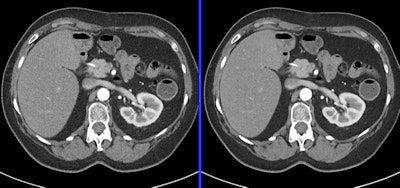

0.2-mSV cardiac CT angiography examination demonstrates standard reconstruction versus iterative model reconstruction (IMR). Image courtesy of Philips Healthcare.Dose-reduction strategies

Mahesh said that maintaining image quality is critical for protocols involving liver or pancreas CT scans, for example. By comparison, CT angiograms, CT colonoscopy, and CT enterography can use protocols with slightly lower image quality.

Use iterative reconstruction algorithm software if it is available.